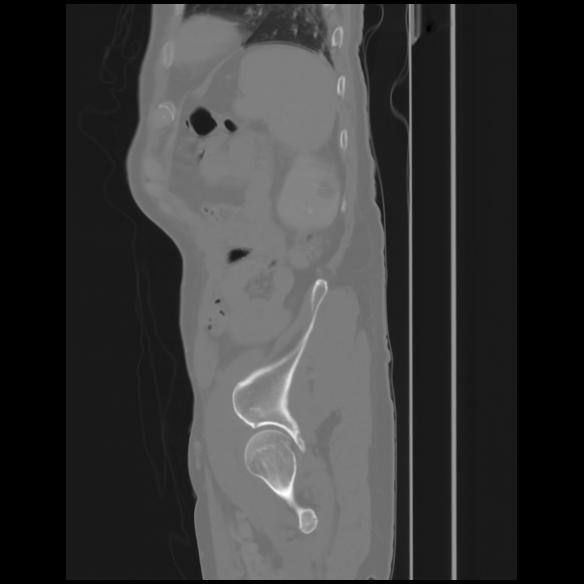

7 CUERPO,CE,Sagittal,3.000,CUERPO,Sagittal,